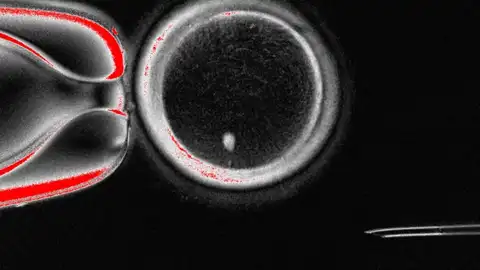

Algunos óvulos creados en el laboratorio fueron fecundados y alcanzaron las primeras fases del desarrollo embrionario. Aunque no prosperaron más allá del sexto día, este estudio demuestra que es posible inducir la formación de gametos humanos mediante reprogramación celular.

El experimento permitió obtener 82 óvulos funcionales, que fueron fecundados con esperma humano. Un 9% alcanzó la fase de blastocisto, correspondiente a los primeros seis días de desarrollo embrionario. Aunque ninguno se cultivó más allá de ese punto, los autores destacan que se trata de una prueba de concepto que demuestra la viabilidad de generar gametos humanos a partir de células somáticas.

El trabajo también señala importantes limitaciones. La mayoría de los embriones no progresaron y se detectaron anomalías genéticas, lo que obliga a realizar más estudios antes de plantear posibles aplicaciones clínicas.

"Todavía no hemos conseguido que los 23 cromosomas correctos se eliminen al formar el corpúsculo polar”, explica Martí. “Esto ocurre porque, al introducir el núcleo de una célula somática en el óvulo, los cromosomas homólogos no se alinean correctamente en el nuevo huso acromático. Al no producirse ese emparejamiento, la separación durante la división genera muchas alteraciones genéticas (aneuploidías) que impiden el desarrollo normal del embrión", añade.